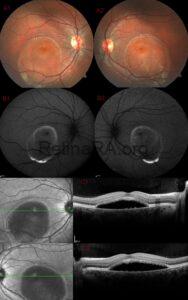

Choroidal osteoma complicated with CNVM

A 16-year-old male patient presented with decreased vision in his right eye. Best-corrected visual acuity [...]